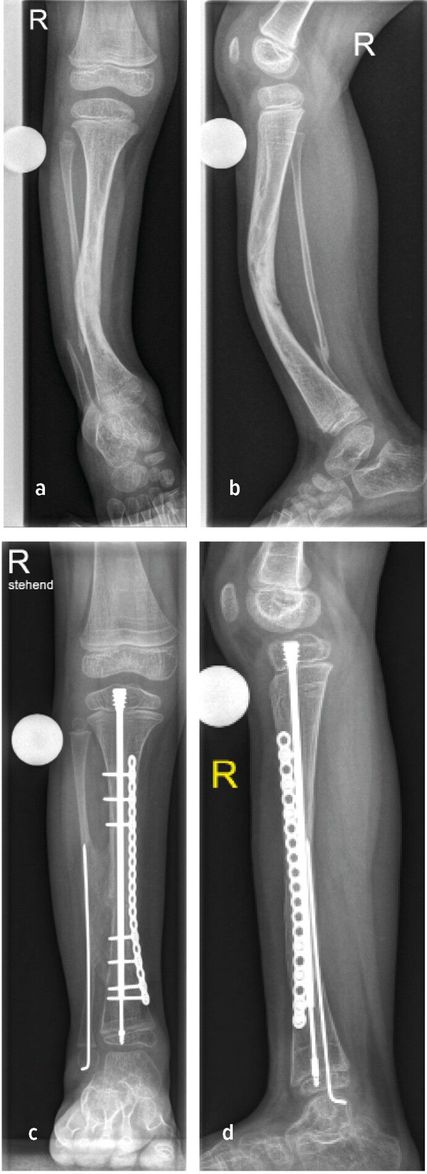

Abb. 2: Präoperative (a+b) sowie postoperative Bildgebung (c+d) eines 5-jährigen Patienten mit CPT

Rezente Klassifikation berücksichtigt die Integrität der Tibia und Fibula, die Stellung der distalen Fibula in der Gelenksgabel sowie das Vorhandensein knöcherner Defekte.11 Sowohl konservative Therapie zur Frakturvermeidung als auch operative Verfahren zur Korrektur der Fehlstellung stehen zur Verfügung: Orthesen, Anlage eines externen Fixateurs, intramedulläre Marknagelung, Transfer einer vaskularisierten Fibula oder Durchführung einer sogenannten Cross-Union (X-Union). Abbildung 2b zeigt hierzu den Fall einer Cross-Union-Operation mit Resektion der Pseudoarthrose, guter Knochenbrücke zwischen Tibia und Fibula (Cross-Union), Stabilisierung der Tibia mit intramedullärem Teleskopnagel und Platte, Stabilisierung der Fibula mit Bohrdraht (Abb.2c,d).11,12